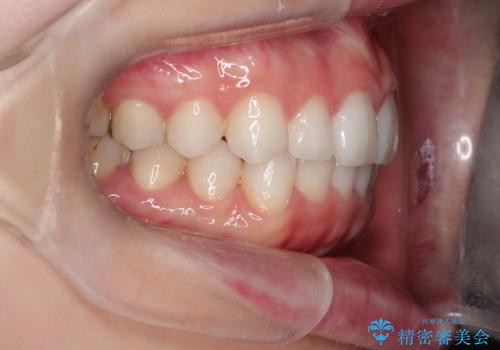

使用時間を守っていただけたので、スムーズに治療を終わることができました。

1周目が終わり、かなり綺麗になりましたがもう少し納得出来るまで続けたいという要望に答えてくださり、今2周目を終え本当に満足いく結果になりました。ありがとうございます。矯正を通して歯は意外と簡単に動くのだなと身をもって感じたのでこれからもリテーナーを怠らずつけ続けたいと思います。